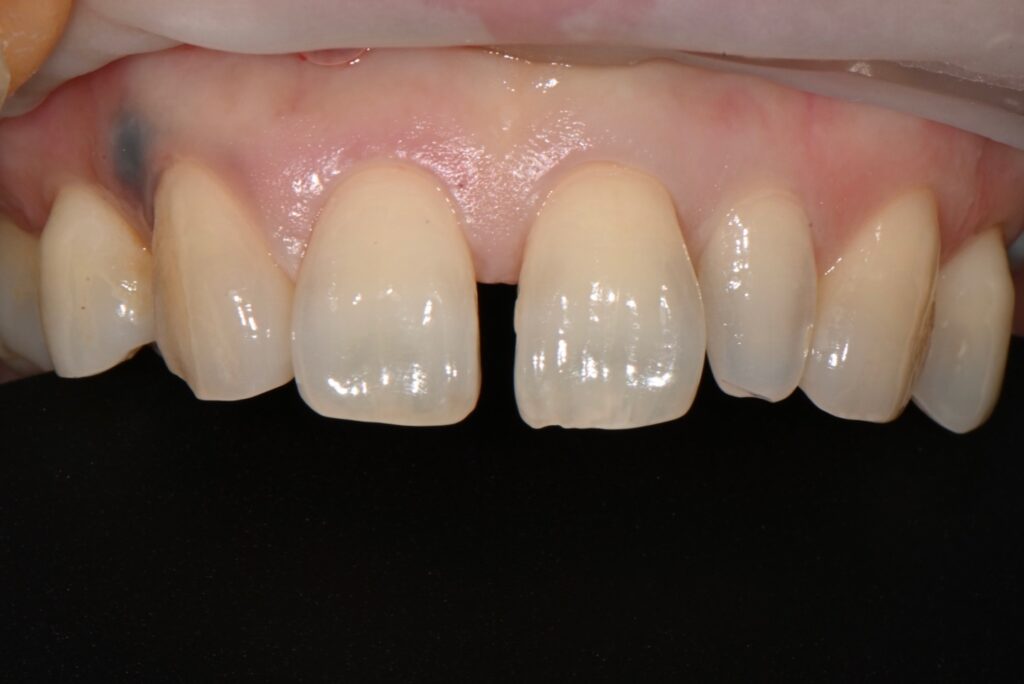

최종 모습입니다

혹시 이상하다고 생각하시는 분들이 있겠지만

측절치 즉 왜소치의 레진성형도 완성이 되어서

치료 후의 모습이라고 보시면 됩니다